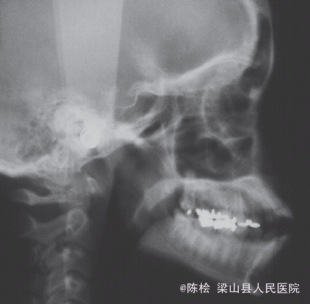

伸舌吞咽习惯,前牙4-4开合3mm,上下牙列散隙

诊断:开合 治疗:双侧第一第二磨牙带环上制作TPA,同时弓丝伸至前牙段弯成腭刺,腭刺破除伸舌吞咽的不良习惯,TPA压低双侧后牙,降低后牙槽高度,改善开合.